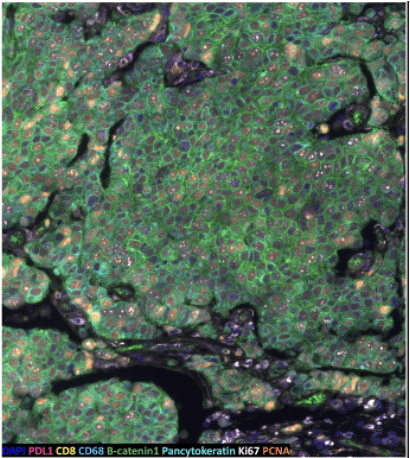

Spatial Proteomics

The aim of the Spatial Proteomics unit is to do full-service multiplexed immunofluorescence (IF) projects covering discovery, translational and diagnostic research questions. The feasibility of proposed projects is assessed, then we perform everything from project design, sample preparation and imaging to give you the best results possible. Initial analysis suport can be given. Our instrumentation and methods allow us to run targeted spatial proteomics analysis of up to 50 markers at single cell level in tissue sections (fresh frozen or FFPE) in human or mouse sections. In the Spatial Proteomics unit, we offer:

In the Spatial Proteomics unit, we offer:

- High-plex IF with Phenocycler-Fusion (Akoya)